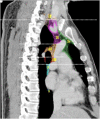

The purpose of this study was to develop a consensus-based computed tomographic (CT) atlas that defines lymph node stations in radiotherapy for lung cancer based on the lymph node map of the International Association for the Study of Lung Cancer (IASLC). A project group in the Japanese Radiation Oncology Study Group (JROSG) initially prepared a draft of the atlas in which lymph node Stations 1-11 were illustrated on axial CT images. Subsequently, a joint committee of the Japan Lung Cancer Society (JLCS) and the Japanese Society for Radiation Oncology (JASTRO) was formulated to revise this draft. The committee consisted of four radiation oncologists, four thoracic surgeons and three thoracic radiologists. The draft prepared by the JROSG project group was intensively reviewed and discussed at four meetings of the committee over several months. Finally, we proposed definitions for the regional lymph node stations and the consensus-based CT atlas. This atlas was approved by the Board of Directors of JLCS and JASTRO. This resulted in the first official CT atlas for defining regional lymph node stations in radiotherapy for lung cancer authorized by the JLCS and JASTRO. In conclusion, the JLCS-JASTRO consensus-based CT atlas, which conforms to the IASLC lymph node map, was established.